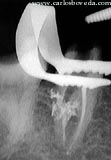

El paciente, de 46 años de edad, en aparente buen estado de salud general, nos es referido para evaluar endodónticamente el primer molar inferior derecho.

Estas opiniones de nuestros participantes reflejan sus criterios: Participante 1.- " É um dente com tecido pulpar com diminuição de volume fisiológica, tanto em razão do tempo de permanência do mesmo na cavidade bucal quanto das forças físicas que atuam no mesmo em razão de suportar uma coroa protética. Radiograficamente apresenta uma área radiolúcida na região do canal distal, sugerindo um processo de reabsorção interna. ". Participante 2.- " La evaluación clínica nos revela una evidente alteración del tejido pulpar, muy probablemente como resultado al tallado realizado en el molar. Sin observar la imagen radiográfica podríamos pensar inicialmente en una calcificación de ese tejido, sin embargo, radiográficamente esa alteración se evidencia como una resorción interna en la porción coronaria del conducto distal, y que aparentemente aún no ha involucrado el periodonto. ". Participante 3.- "creo que la raíz mesial , sus conductos se encuentran calcificados por lo que se observa radiograficamente. El conducto distal presenta una reabsorción interna a nivel de tercio cervicaly medio. ". Participante 4.- "Para mì es una pulpa stressada, al recibir el tallado para la corona. En las raìces mesiales, la pulpa reacciona calcificàndose, mientras que en raìz distal aparenta tener una reabsorciòn interna (digo aparenta, porque no puedo ver en la imàgen detalladamente, las caracterìsticas de dicha reabsorc.)Quizàs, el tallado ocasionò una hemmorragia pulpar, que termina en u na reabsorc. ". Participante 5.- "Por el estado clínico y radiográfico de la hemiarcada se puede deducir que este diente ha estado con una mala función por mucho tiempo, soportando todas las fuerzas antes de recibir los implantes en los premolares, por lo tanto ha sufrido cambios importantes en su anatomía radicular, en mi manera de ver, este diente esta sufriendo un proceso de anquilosis y calcificación de los conductos en la raíz mesial,en la raíz distal se puede observar una pequeña luz del conducto con una zona radiolúcida en el tercio cervical posiblemente sea una zona de reabsorción interna, no se puede definir claramente el ligamento periodontal y el tejido radicular se confunde con el tejido óseo, por obvias razones su respuesta a las pruebas de vitalidad están disminuídas ". Participante 6.- " Pareciese haber una resorcion en el tercio medio y coronal de la raiz distal ya sea interna o externa habria que verificar tomando rx mesioradial y distoradial para verififcar si la imagen se desplaza, la respuesta disminuida podria deberse a que alguno de los filetes todavia permanezca con vitalidad. ". Participante 7.- " este molar para mi tiene buen pronostico sin realizarle tratamiento de conductos, por lo que veo radiograficamente y la sintomatologia me hace pensar en una degeneracion calcica, y no veo la razon de realizarle tratamiento de conductos ". Participante 8.- " el molar radigraficamente no se observa conductos en la raiz mesial lo que nos indica una posible metamorfosis calcica, teniendo en cuenta la disminucion de respuesrta ante el estimulo termico. En las raices distales se observa una rarefacion en el tercio coronal del conducto, ". Participante 9.- " Desde el punto de vista radiográfico, este molar parece que tiene una calcificación de los conductos radiculares, la cual podría ser una razón de la dinminución en la capacidad de respuesta ante un estímulo químico o físico, ya que, la conducción nerviosa a travez de los conductos radiculares está disminuida. Por otra parte no se observa ninguna evidencia de afeccion apical ó periodontal. Otra prueba factible de la cacificación de los conductos es la edad del paciente, y la pieza estudiada. ". Participante 10.- "Pulpa sana. LO que llama la atencion es un agrandamiento de la entrada del conducto distal, que en realidad puede llegar a ser una bifurcación del cond. Distal ". Participante 11.- " Pulpa normal ". Participante 12.- " Molar inferior con dos raices , en la raíz distal se observa una zona radiolúcida en tercio cervical de aproximadamente de 1 cm de longitud, posiblememnte compatible con Reabsorción interna. Aparentemente los conductos mesiales se encuentran calcificados ( degeneración Pulpar Calcificante) ". Participante 13.- "aunque radiográficamente no se observa ensanchamiento del espacio del ligamento periodontal, ni ninguna imagen periapical, se observa disminución en el tamaño de la cámara pulpar y de los conducto radiculares por procesos de calcificación, lo que evidencia degeneración pulpar. ". Participante 14.- "Hay una clara retracción pulpar pero en cuanto alos conductos se refiere, parecen estar en una situación aparentemente normal. ". Participante 15.- " La situación pulpar de este molar, podría ser la de una rebsorción dentinaria interna (conducto distal), probablemente en los conducto mesiales tengamos una calcificación, todo esto por una alteración pulpar posiblemente causada por una mala refrigeración al tallado del muñon coronario. ". Participante 16.- "En los conductos mesiales y la cámara pulpar, existe una aparente calcificación parcial, mientras que en el conducto distal, se observa una aparente resorción interna; producto de un proceso inflamatorio crónico irreversible. De hecho responde a las pruebas térmicas, pero de forma disminuida debido a ese proceso crónico y a la aposición de dentina. Estamos en presencia de una pulpitis irreversible. ". Participante 17.- "Este molar aparentemente presenta una reacción pulpar inflamatoria, en donde el órgano pulpar reaccionó como medio de defensa con una resorción interna a nivel del conducto distal y una calcificación parcial de la pulpa a nivel de los conductos mesiales. ". Participante 18.- " Después de analizar los datos suministrados, este molar presenta un diagnóstico provisional de Pulpitis irreversible, ya que radiográfica y clínicamente hay evidencia de degeneración pulpar por la aparente calcificación de la cámara y de los conductos y por la imagen sugerente de resorción interna (sin embargo esto no se puede asegurar, se necesitarian radiografías con otras angulaciones). ". Participante 19.- "Debido a las imágenes radiográficas,las cuales sugieren la presencia de una resorción interna en el conducto distal y la presencia de calcificaciones y las respuestas obtenidas en las pruebas térmicas podemos diagnosticar la presencia de una pulpitis irreversible asintomática. ". Participante 20.- "De acuerdo a las imágenes radiográficas, a la sintomatología y a los resultados de las pruebas clínicas reportados, el molar observado presenta una pulpitis irreversible asintomática, por lo que se indicaría la realización de un tratamiento endodóntico previo a la confección de la restauración definitiva. ".

Nuestra actitud frente al caso : Coincidimos con la opinión de la mayoria de los participantes de este for, en el sentido que las evidencias muestran una pulpa patológica, particularmente por la resorción interna evidente en el conducto distal, por lo que se considera necesario ejecutar el tratamiento endodónticoÑ